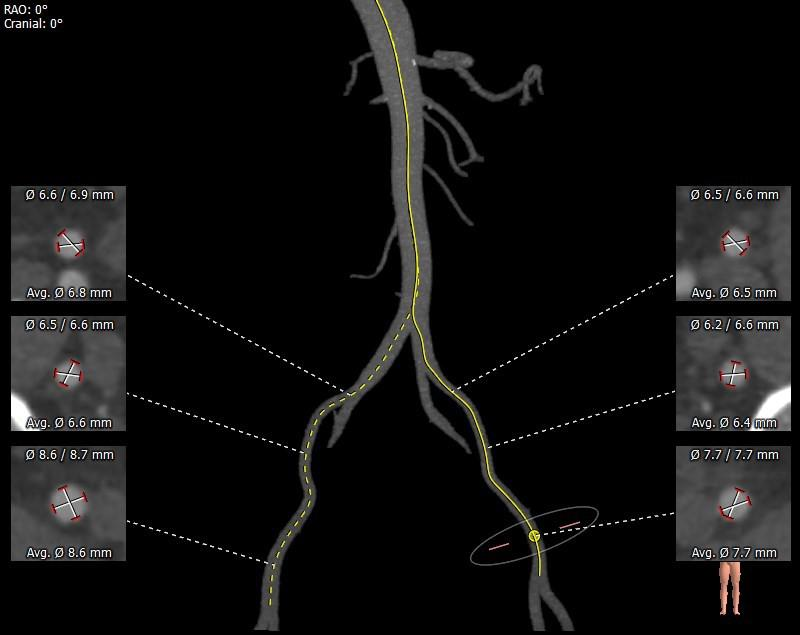

外周分析